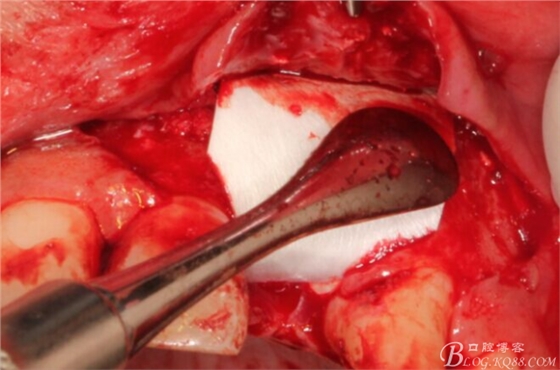

先行粘骨膜減張,取自體血液。

根方用取骨鉆取自體骨。